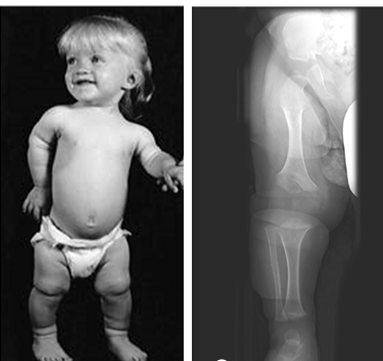

what is the condition?

chondroplasia (or pseudochondroplasia) activating mutation in FGFR3 (fibroblast growth factor) that impaired proliferation of cartilage in the growth plate leading to shorter long bones